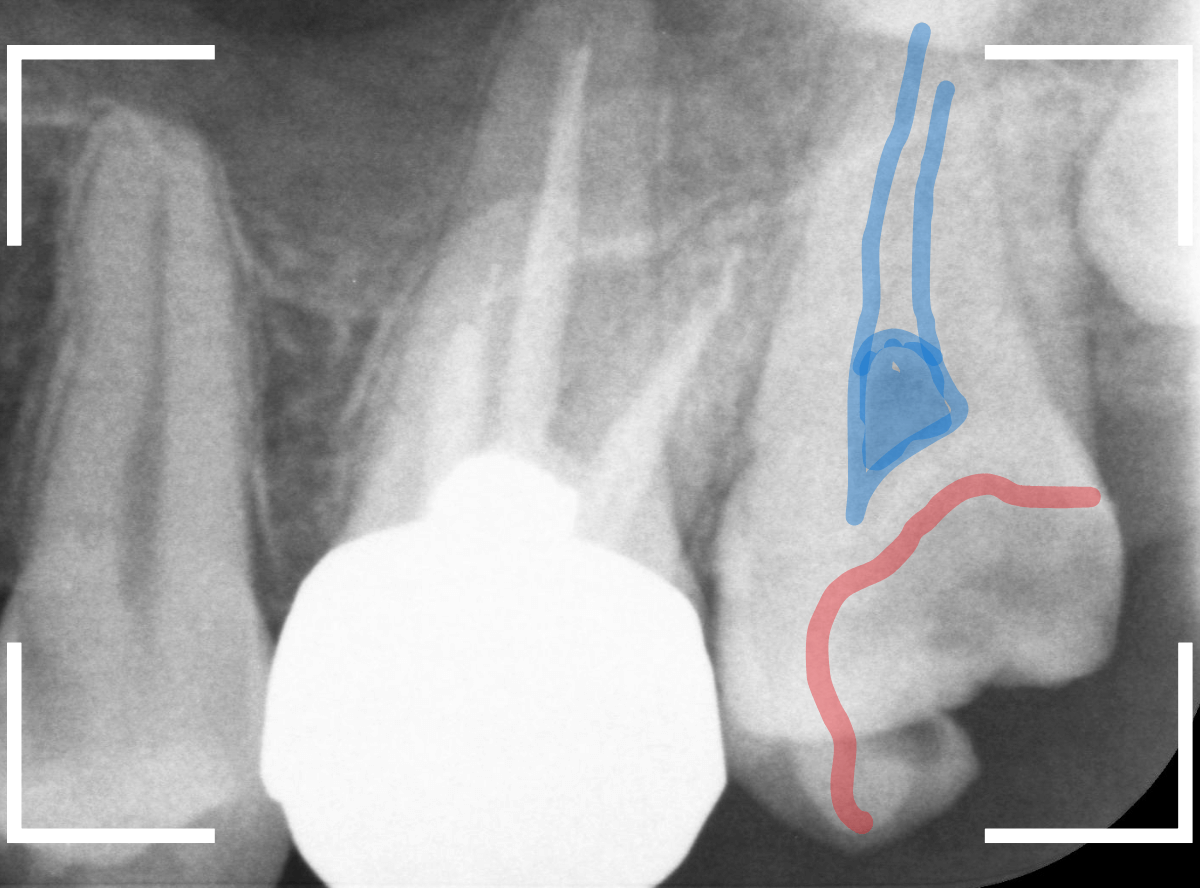

レントゲン写真で確認します。

青い線が歯の神経、赤い線が虫歯です。

おやしらずがあった際にはわかりづらかったですが、歯の後ろ側のおやしらずが重なっていたところが虫歯になっているのがわかります。

おやしらずが原因で、このように手前の歯が虫歯になってしまう事が多いために、抜歯を勧められる事が多いのです。

そして、虫歯の部分におやしらずが被さっていたために、しみる症状などを感じなかったのです。